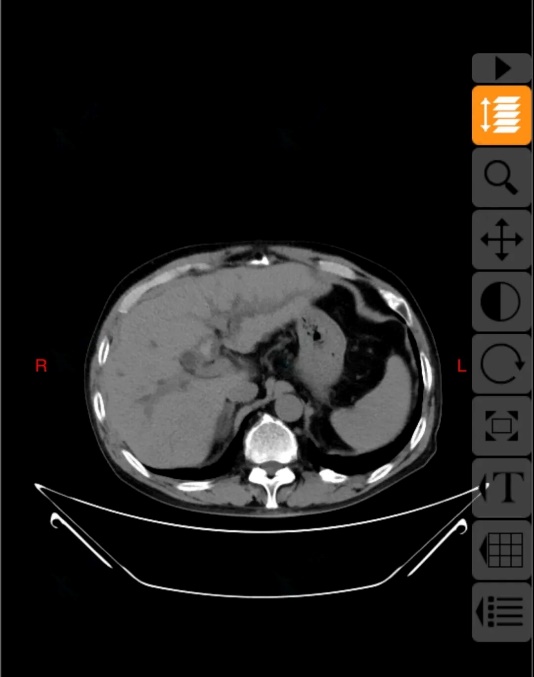

前几日,患者在当地医院复查上腹部CT,结果提示“胆总管结石、肝内胆管结石”。为求进一步诊治,患者慕名来到东院区肝胆外科就诊,以“胆总管结石”将其收治入院。因患者病情复杂、手术史特殊,科室高度重视,沙焕臣主任组织科室骨干力量多次进行病情讨论及全面术前评估。医疗团队在系统分析患者历次手术资料及最新影像学检查后指出,患者因多次手术导致腹腔广泛粘连、解剖结构紊乱,同时肝内胆管结石位置高、分布广泛,若采用传统手术方式,不仅难以彻底清除结石,也无法有效解决胆汁引流问题,手术难度及风险极高。

10月17日,在麻醉手术部团队的密切配合下,沙焕臣主任主刀手术,术中发现腹腔内粘连严重,肠管、大网膜与腹壁、肝脏广泛致密粘连。手术团队精细操作,逐步分离粘连,成功显露肝门区及胆总管。随后在胆道镜辅助下,彻底清除胆总管及部分肝内胆管结石。针对左肝外叶多发结石伴局部胆管狭窄的情况,团队实施了肝左外叶切除,并对高位胆管进行精细修补与成形,最后顺利完成胆肠吻合术,重建胆汁引流通道。手术过程顺利,术中出血量控制良好,患者生命体征平稳,术后患者安全返回病房。在护理团队的精心照护下,患者恢复进程良好,未出现胆漏、出血、感染等并发症,目前已顺利过渡到流质饮食阶段,并开始逐步下床活动,身心状态稳步改善。